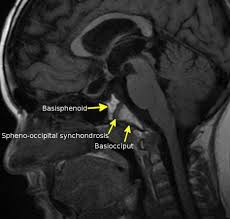

さらに首の中央を通過すると頭蓋骨の底辺に当たります。ここには後頭骨と蝶形骨の接点(ゲート)があって、クラニオセイクラル・セラピーでは非常に重要視する部位なんです。